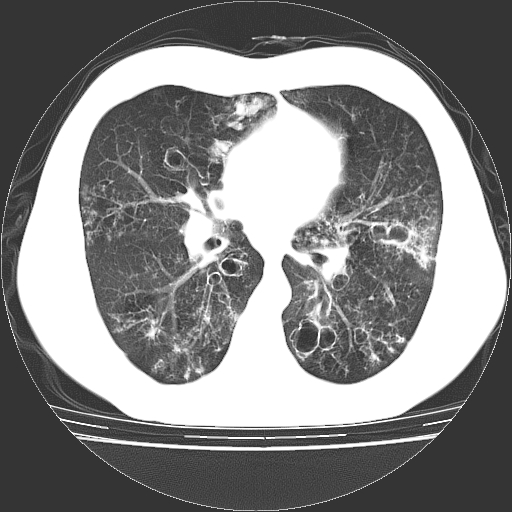

以下是引用zyx168在2006-12-4 15:30:00的发言:[br]经典!支气管肺囊肿并感染。

以下是引用dyqct在2006-12-4 17:11:00的发言:[br]典型的囊状支扩合并感染。

以下是引用liaoqiang在2006-12-4 16:12:00的发言:[br]局部肺叶内可见扩张的支气管壁,考虑为支扩。部份囊样影内有小液平和肺内散布斑片征影、小结节及纤维灶,提示支扩伴感染,且由于局部呈现有树芽征感染以结核可能性大。

以下是引用zhoucan076在2006-12-4 16:48:00的发言:[br]囊状支扩合并感染